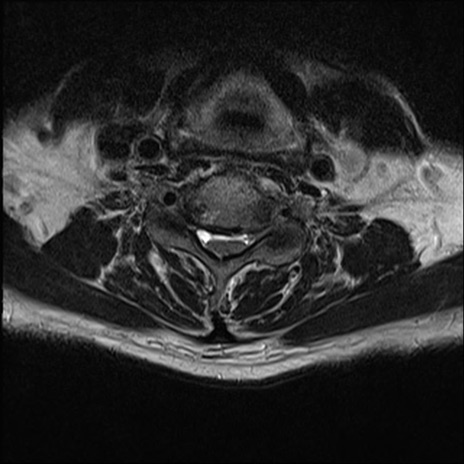

【整形】TIPS症例7 頚椎MRI T2WI(横断像)

頚椎MRI

矢状断像と横断像